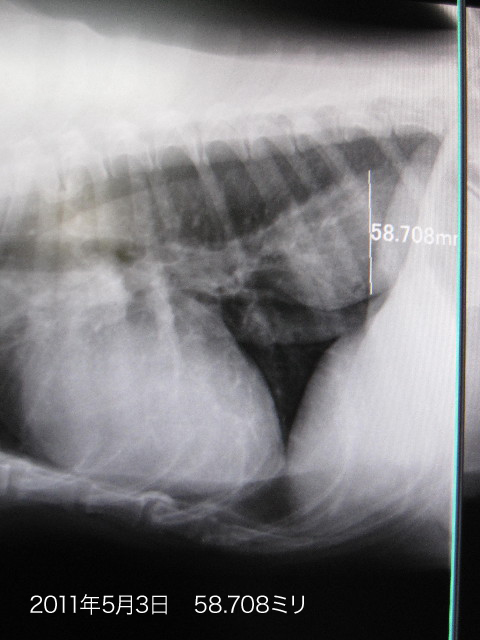

4ケ月ぶりにレントゲンを撮ったら

●哀しいかなべべちゃんのnQちゃんの直径が6.861ミリも大きくなってしまっていました。。。。

(1月4日は51.847ミリ/5月3日は58.708ミリ)